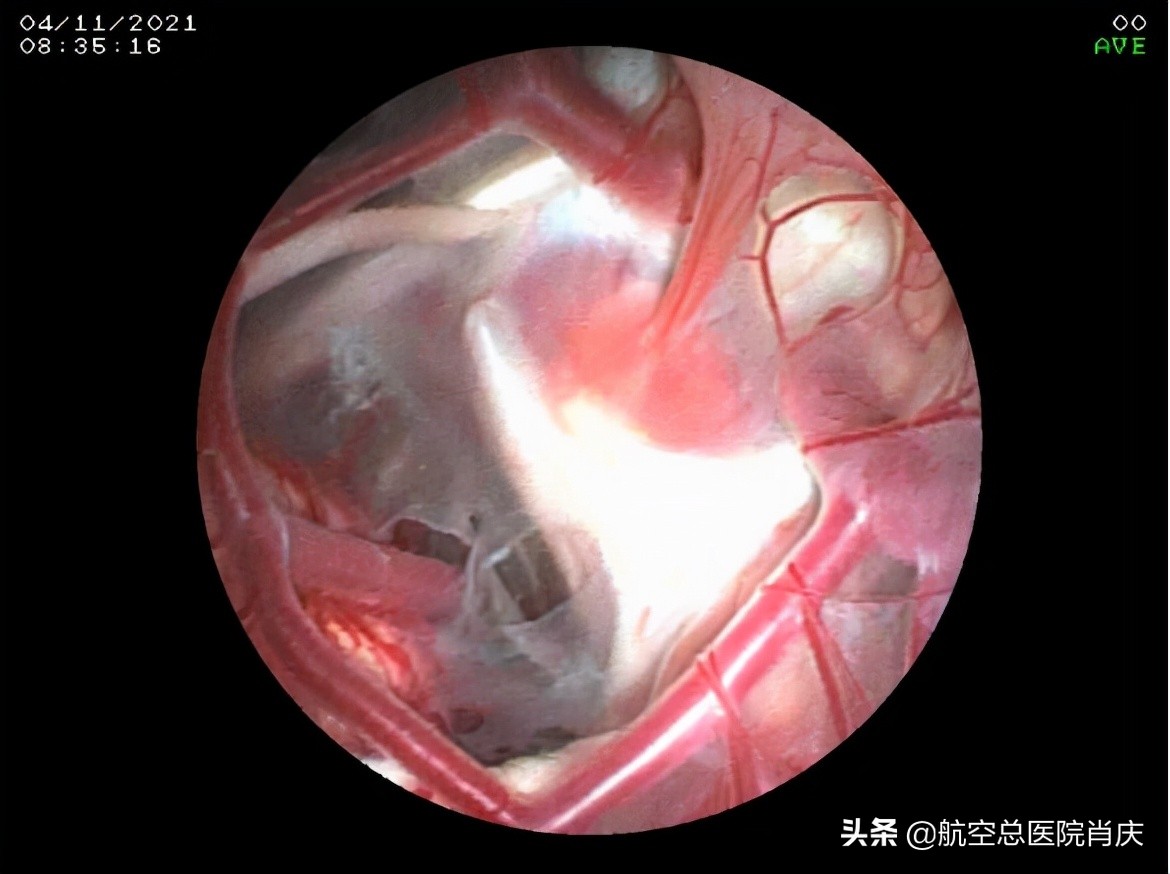

(自基底池所见左侧颞极囊肿壁)

(自基底池所见右侧囊肿壁)

(内镜下鞍上池囊肿底壁造瘘,左侧颞极囊肿-基底池造瘘)

(右侧颞极囊肿-基底池造瘘口)